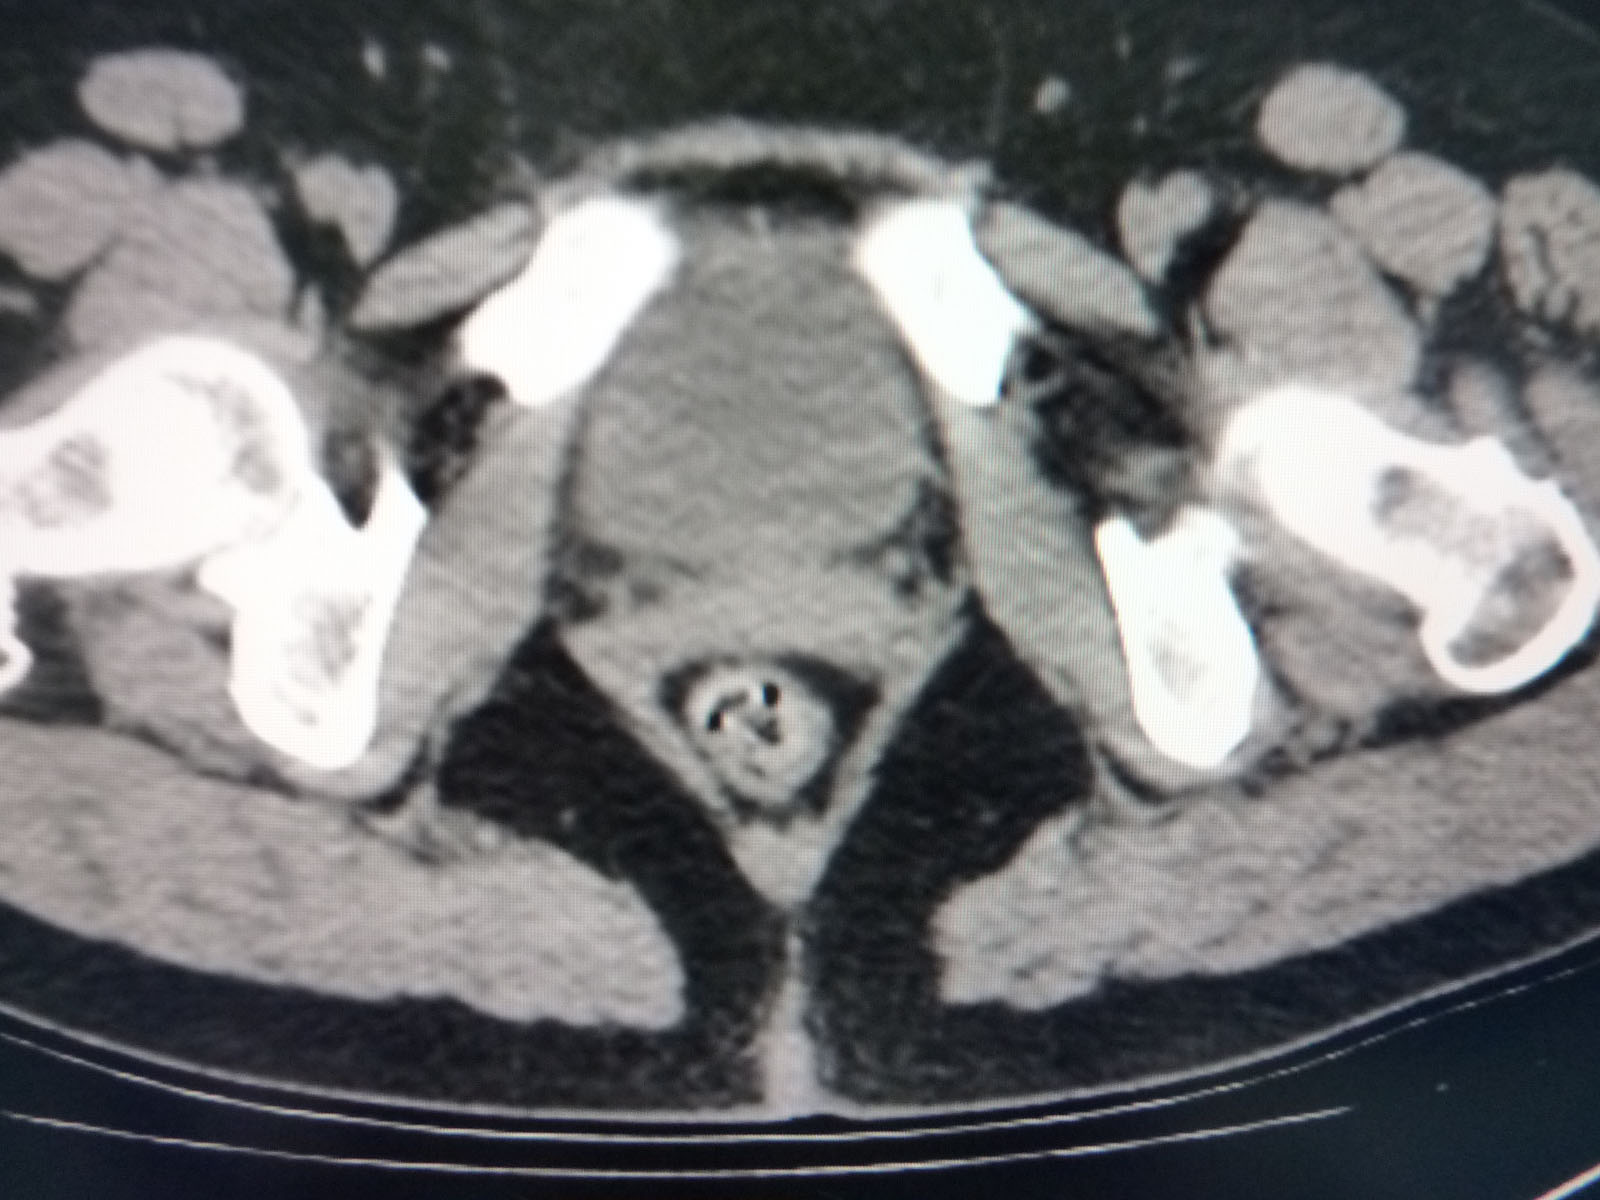

CT49554:体检

子宫正常吧

子宫肌瘤

宫颈管肌瘤